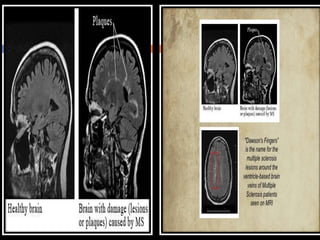

 MS is predominantly a white a matter disease and a

neurodegenerative disorder of the central nervous

system that includes the brain, spinal cord and nerves